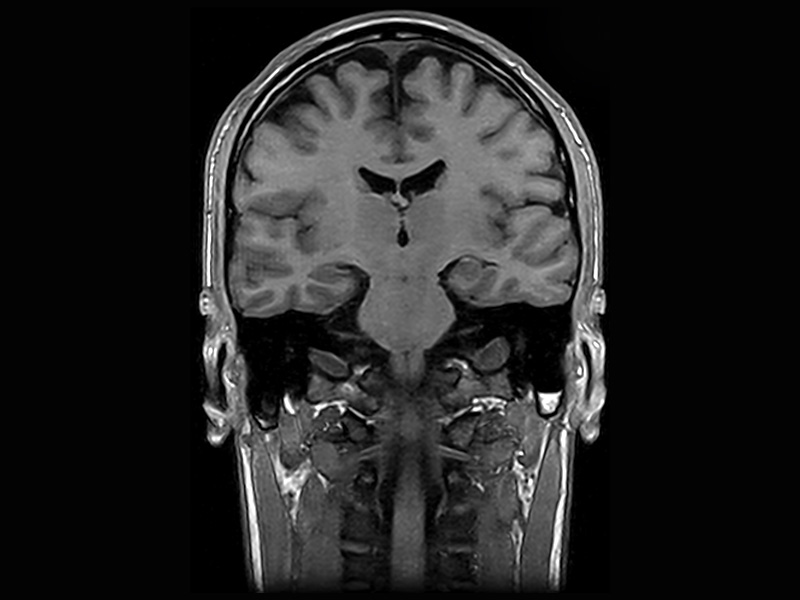

Klinické snímky